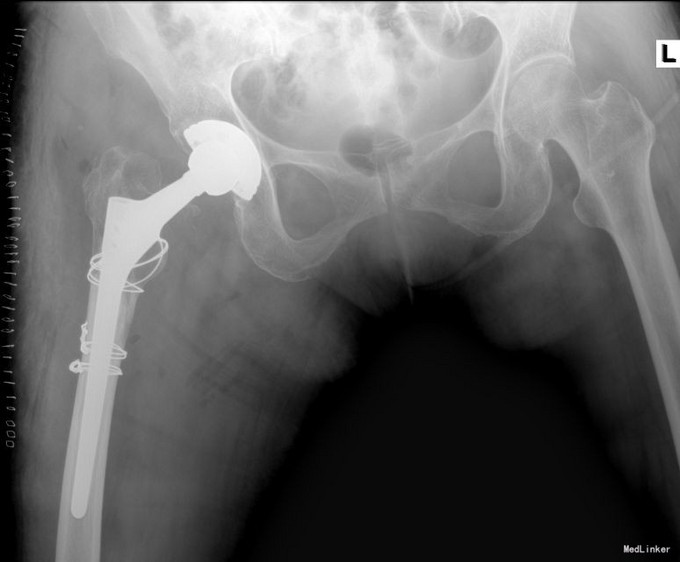

望:神志清,精神尚可,面色红润,营养良好,体型中等,舌红,苔薄黄;闻:语声清晰,呼吸均匀,未闻及特殊气味;切:脉弦紧。平车推入病房。右下肢较对侧未见明显短缩,外旋畸形,肌肉未见明显萎缩,右腹股沟饱满,腹股沟及大转子处压痛明显,右髋关节活动不能,“4”字实验因患者疼痛拒查,右下肢纵向叩击痛阳性,双下肢肌力未见明显异常。双下肢皮肤感觉未见明显异常,末梢血液循环尚可。X线检查:右侧人工全髋关节置换术后假体周围骨折。

中医诊断:1、右侧全髋关节置换术后假体周围骨折(气滞血瘀)2、眩晕 3、胸痹心痛 4、陈旧性脑梗 5、骨痿 6、动脉粥样硬化症 7、白内障 8、房颤 西医诊断:1、右侧全髋关节置换术后假体周围骨折 2、高血压 3、冠心病 4、陈旧性脑梗 5、骨质疏松 6、动脉粥样硬化症 7、白内障 8、房颤 诊疗计划:1、择期行全髋关节翻修术;2、中医辨证论治:根据骨伤科三期辨证理论,早期因瘀血停滞影响骨痂生长,故以活血化瘀,消肿止痛为主,应用桃红四物汤;中后期补益肝肾,补气养血,应用愈骨胶囊等药物应用。现患者属于骨折早期,可运用桃红四物汤加减对症治疗,方药如下: 桃仁10g 红花10g 当归12g 川芎12g 白芍12g 穿山甲6g 柴胡12g 黄芩10g 延胡索15g 续断15g 生地12g 甘草6g 3付 用法:每日一剂,水煎服400ml,分早晚两次温服。 3、中医调护:避风寒,慎起居,忌生冷,畅情志。

术后复查X线片示假体位置良好,固定牢靠。根据中医辨证论治:中医辨病辨证依据:该病因直接暴力作用,致骨挫筋伤,而致气滞血瘀,经络受损,瘀阻经络,证属气滞血瘀。舌质淡,苔薄白为病邪尚未入里,脉弦,主瘀,主痛,亦为“气滞血瘀”之征象。术后嘱患者中医调护:避风寒,调饮食,慎起居,畅情志;保持切 口清洁,预防感染,注意饮食营养,多吃蔬菜、水果及含蛋白质高的食品,不能进食辛辣刺激类食物。继续口服药物治疗。继续抗炎、抗凝、抗骨质疏松治疗,预防关节术后并发 症;如遇身体局部及全身感染,及时就诊,继续口服利伐沙班或阿司匹林预防血栓性疾病。药物对症处理,适当功能锻炼,主动被动进行关节的 伸直,弯曲,直腿抬高训练,促进关节功能恢复;积极治疗内科基础病,控制血压,预防内科并发症,复查切口愈合情况。避免跪姿,跑跳,深蹲等剧烈活动,按时复诊;助行器使用到复查。不适随诊。本病例中医药应用结合手术治疗,可迅速缓解患者症状,恢复患肢功能,加快术后恢复,可使患者获得满意的术后疗效。